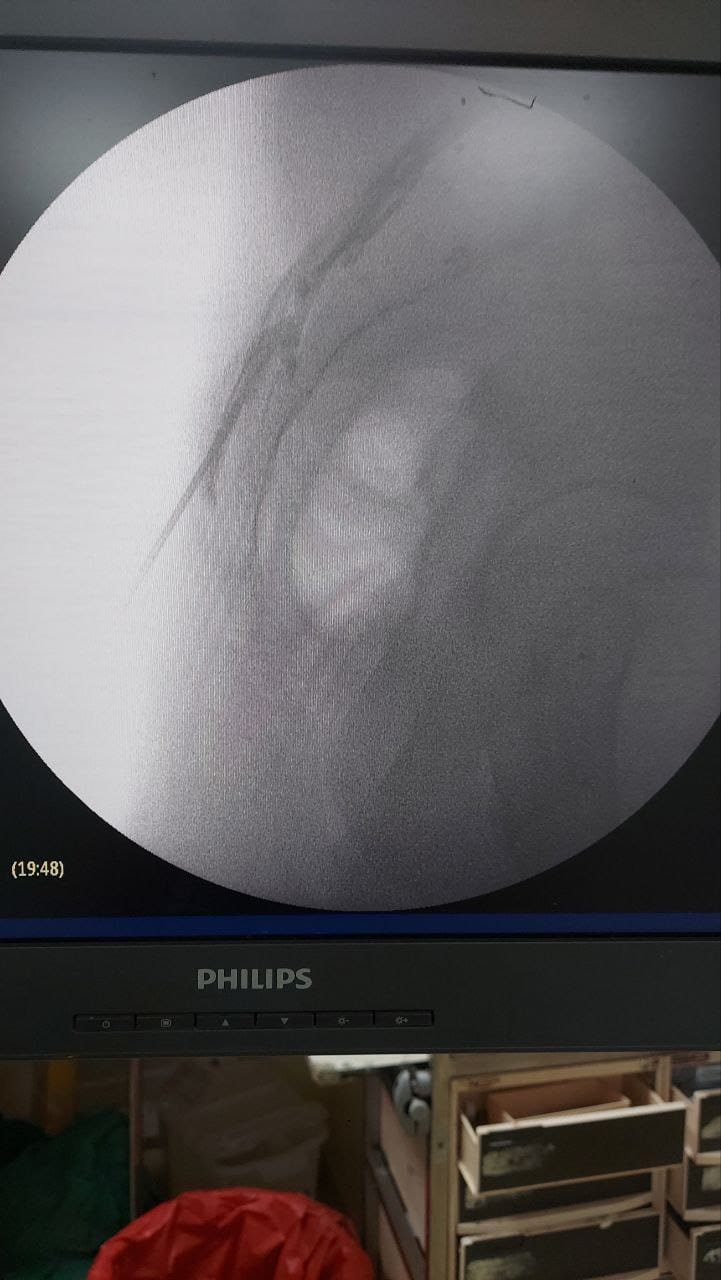

Procedures

Struggling with chronic pain? Get advanced, personalised pain management from Dr. Manish De, one of Kolkata’s leading pain specialists. From knee pain, heel pain, low back pain, frozen shoulder, migraines, cancer pain to post-TKR persistent pain—Dr. De offers safe, evidence-based treatments across multiple locations: